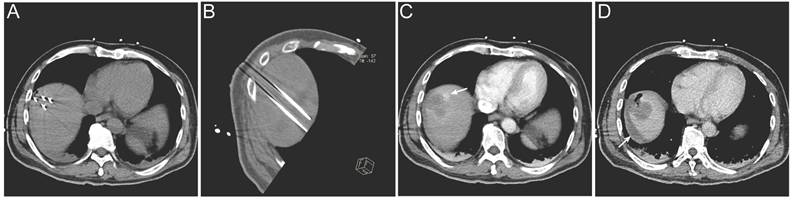

Lesions located in high-risk anatomical regions were comparably distributed between the two groups, with 7 lesions in the IRE group and 6 lesions in the RFA group; however, lesions in the IRE group were more frequently adjacent to major vessels or the hepatic hilum (Table 4). Regarding treatment safety, no deaths within 30 days after treatment were recorded and no severe complications were observed in the RFA group. In the IRE group, one patient developed ablation-related bile duct dilatation and four patients experienced hemorrhage. All adverse events were successfully managed with routine symptomatic treatment (Table 3). A representative case is shown in Figure 6. Intra-procedural images demonstrate electrode placement (Figure 6A, B). Post-ablation arterial-phase imaging demonstrates focal contrast extravasation at the ablation margin, and perilesional fluid attenuation is observed on delayed-phase imaging (Figure 6C, D).

Figure 6

Representative imaging of procedure-related complication following IRE treatment. (A, B) Intra-procedural electrode placement shown on an axial CT image (A) and an oblique multiplanar reconstructed (MPR) CT image (B); (C) Immediate post-ablation arterial-phase contrast-enhanced CT demonstrating focal contrast extravasation at the ablation margin (arrow); (D) Post-ablation delayed-phase contrast-enhanced CT demonstrating perilesional fluid attenuation (arrow).